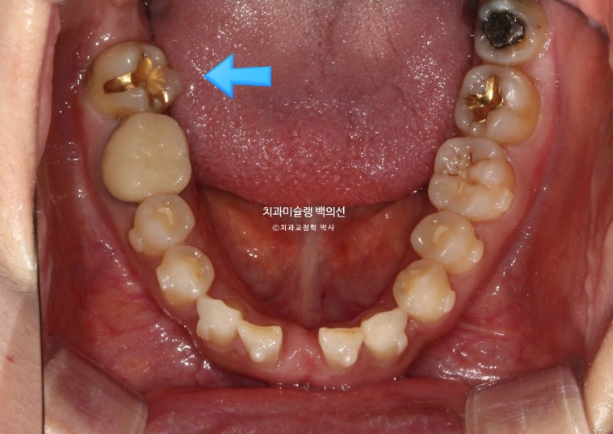

환자분이 모르고 있던 또 다른 문제는 파란화살표 제 2대구치가 혀쪽으로 쓰러져 있는 것 입니다.

파란화살표 쓰러져있던 큰어금니는 꽤 많이 섰습니다.

쓰러져 있던 두번째 큰어금니는 잘 세웠습니다.